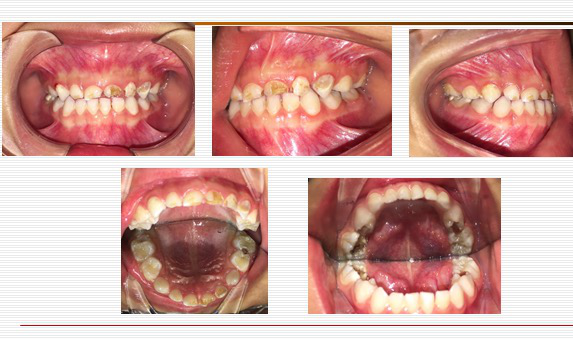

日常主要诊疗内容有:儿童龋病综合防治;儿童牙髓病根尖周病诊治;乳磨牙金属预成冠修复;乳前牙美容修复;儿童牙外伤诊治;儿童牙齿发育异常诊治;儿童咬合异常早期干预;氟化物涂布、窝沟封闭;儿童及青少年牙颌畸形预防及矫正治疗;无痛微创治疗技术、镇静及全麻下儿童牙齿治疗等。